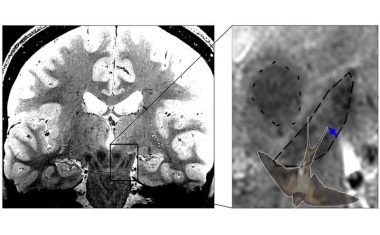

Eine umfangreiche Studie der CritMET-Arbeitsgruppe unter Leitung von Prof. Michael Bau, Geochemiker an der Constructor University in Bremen, zeigt eine großflächige Verunreinigung von Nord- und Ostsee mit MRT-Kontrastmitteln.